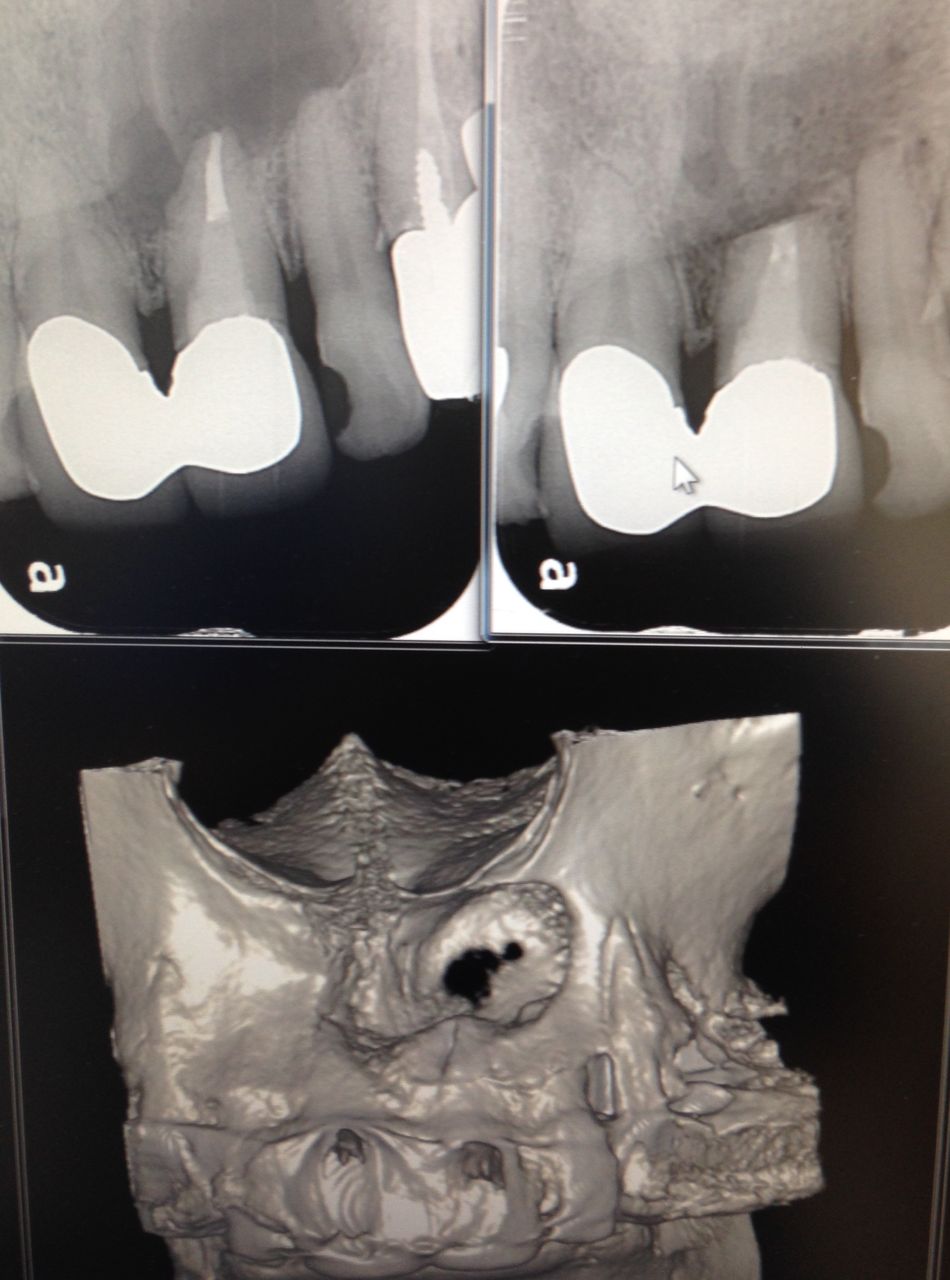

こんなに大きな穴でも、治ります。

少し根っ子を削るので、短くはなりますが。